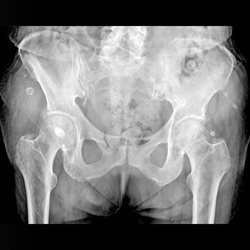

Proximal Femur 3

Radiograph and CT of same patient.